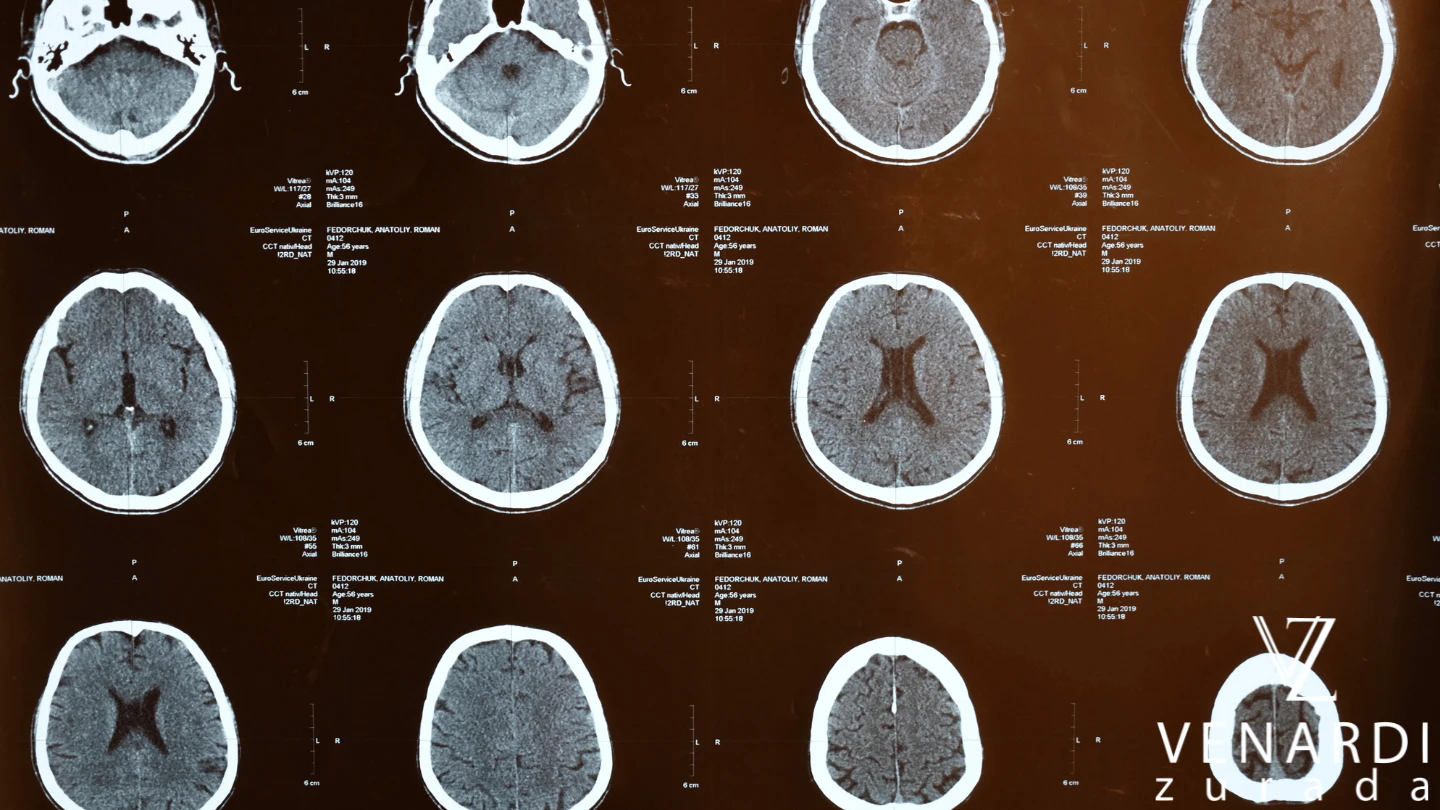

The brain is the control center of the human body, so you can guess that trauma from a blow, bump, penetration, or other violent impact can have catastrophic effects for the victim. The US Centers for Disease Control and Prevention (CDC) report that traumatic brain injury (TBI) leads to around 61,000 fatalities every year and is a top cause of disability for those who survive. Some victims will experience short-term implications, while others may suffer from effects for years or the rest of their lives.

The long-term complications for someone with TBI can vary greatly because they depend upon the severity of the trauma and location of the injury. A minor TBI, such as a concussion, might lead to dizziness, mood swings, blurred vision, headaches, and memory loss. Severe head injuries might mean permanent brain damage, paralysis, and cognitive disorders. In some cases, a victim may lose independence and be reliant on others for care.